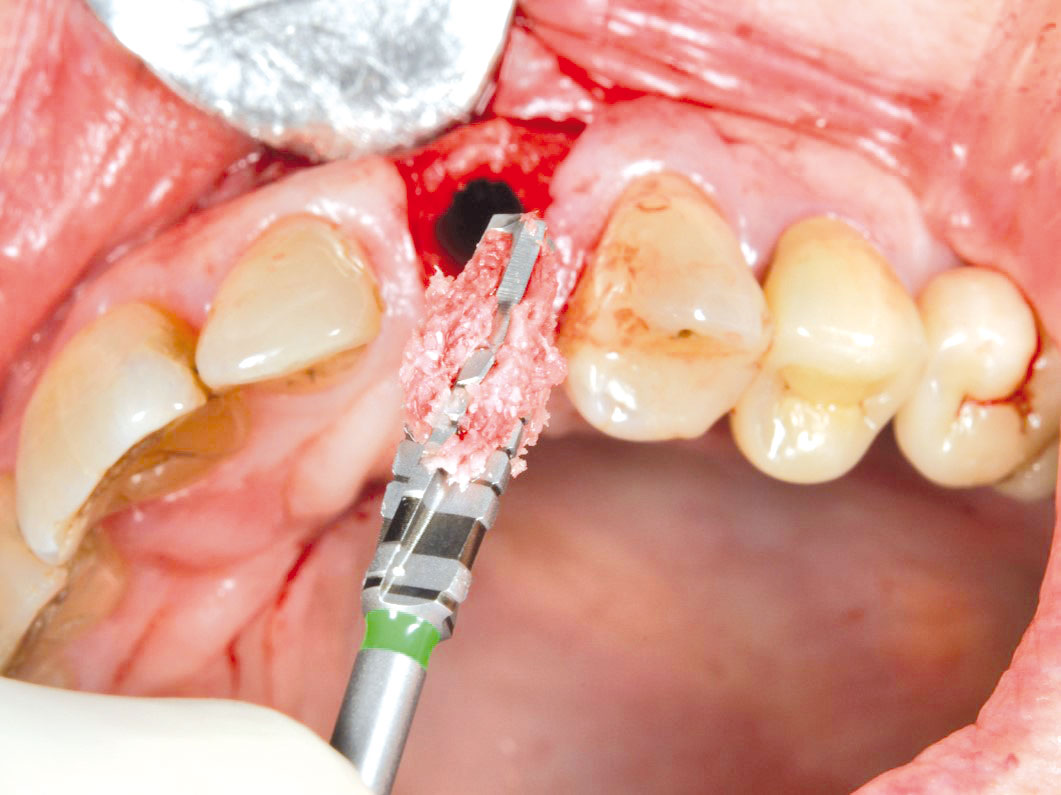

GBR with cerabone® and Jason® membrane in the front tooth region - Dr. H. Maghaireh

Initial clinical situation with gum recession and labial bone loss eight weeks following tooth extraction